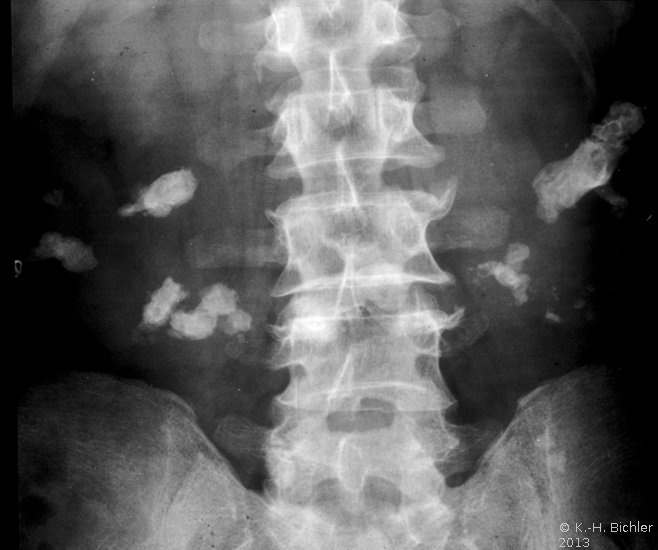

Der Patient kam mit Zeichen eines schweren, fieberhaften Harnwegsinfektes in unsere Behandlung. Die Diagnostik mit Sonographie und Ausscheidungsurogramm sowie Angiographie ergab eine ausgedehnte Harnsteinbildung beiderseits, wobei es im linken Nierenanteil zu Harnabflussbehinderungen gekommen war. Die Abbildungen zeigen die diagnostischen Maßnahmen. Der linke Nierenanteil wurde wegen erheblichen pyonephrotischem Umbau entfernt.

d